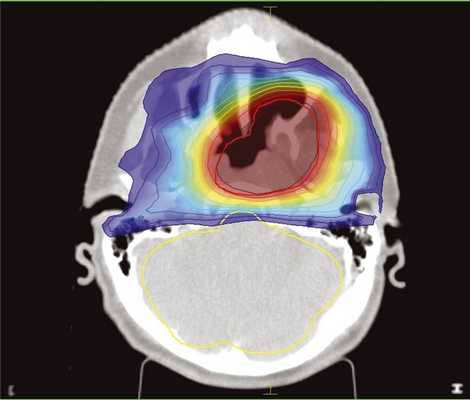

С учетом близкого расположения к мишени нормальных органов и тканей и с целью минимизации воздействия на них была выбрана методика облучения с модуляцией интенсивности пучка (IMRT) (рис. 1 и далее).

Рис. 1. Дозное распределение при повторном облучении очага в носоглотке методикой IMRT. Градиентом цвета обозначен переход от максимальной дозы (красное) к минимальной (синий цвет, 10% от максимальной). Покрытие мишени (PTV) не менее 95%.

Разовая очаговая доза (РОД) составила 3 Гр, поскольку проведение лучевой терапии в традиционном режиме по 2 Гр на уже облученные опухоли является, на наш взгляд, малоэффективной. Гипофракционирование дозы позволяет лучше воздействовать на пул радиорезистентных клеток, повышая эффективность лечения в целом. СОД составила 48 Гр (EQD2 =57,6 Гр). Интервал выбора СОД при повторном облучении рецидивов, по мнению разных авторов, должен составлять эквивалент не менее 50—60 Гр в традиционном режиме. Одной из сложных и дискутабельных проблем при повторном облучении является определение толерантности опухоли и местных тканей при измененных режимах фракционирования (соотношения α/β). Поскольку консенсуса в отношении данного вопроса в доступной нам литературе нет, мы выбрали значение α/β, равное 3, так как оно наиболее точно, на наш взгляд, отражает токсичность лечения.